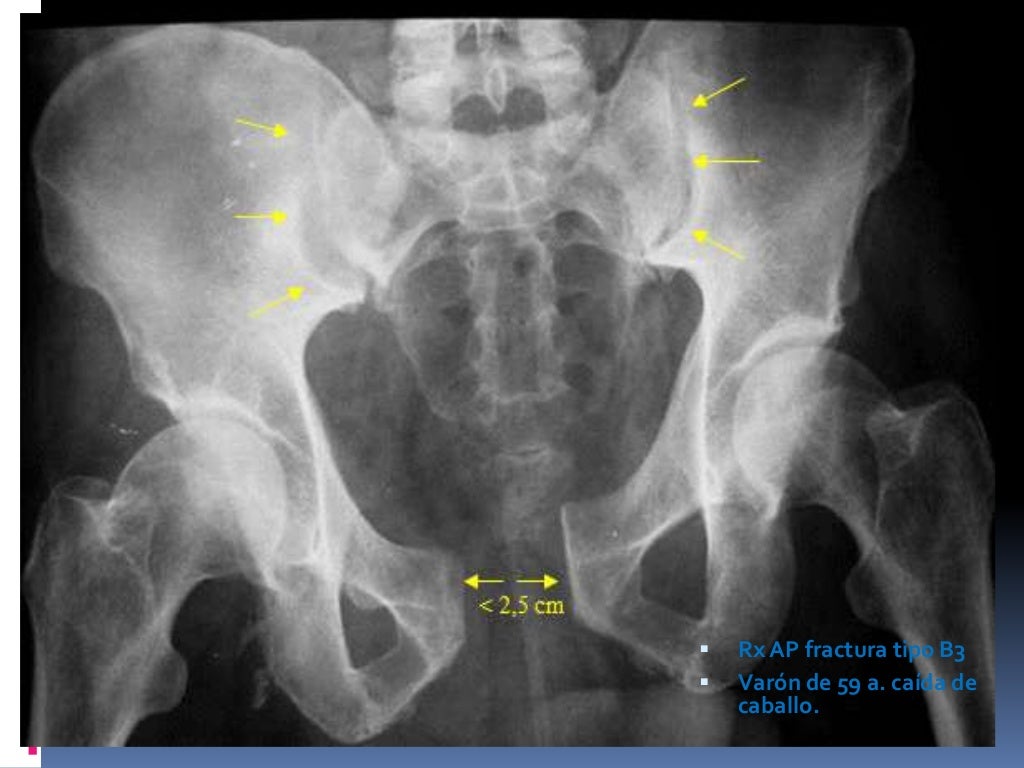

- Fracturas tipo B. Son lesiones inestables que se clasifican en varios subtipos según la localización. Precisan tratamiento quirúrgico.